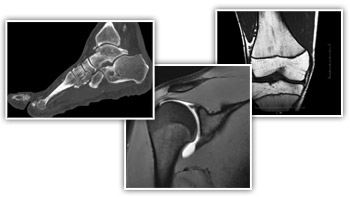

MRI technology has progressed at a rapid rate and many new techniques have been introduced that have a significant impact on patient care. We specialize in outpatient imaging and offer advanced MRI technology in the field.

New imaging technology for advanced diagnostic procedures

• High-image quality